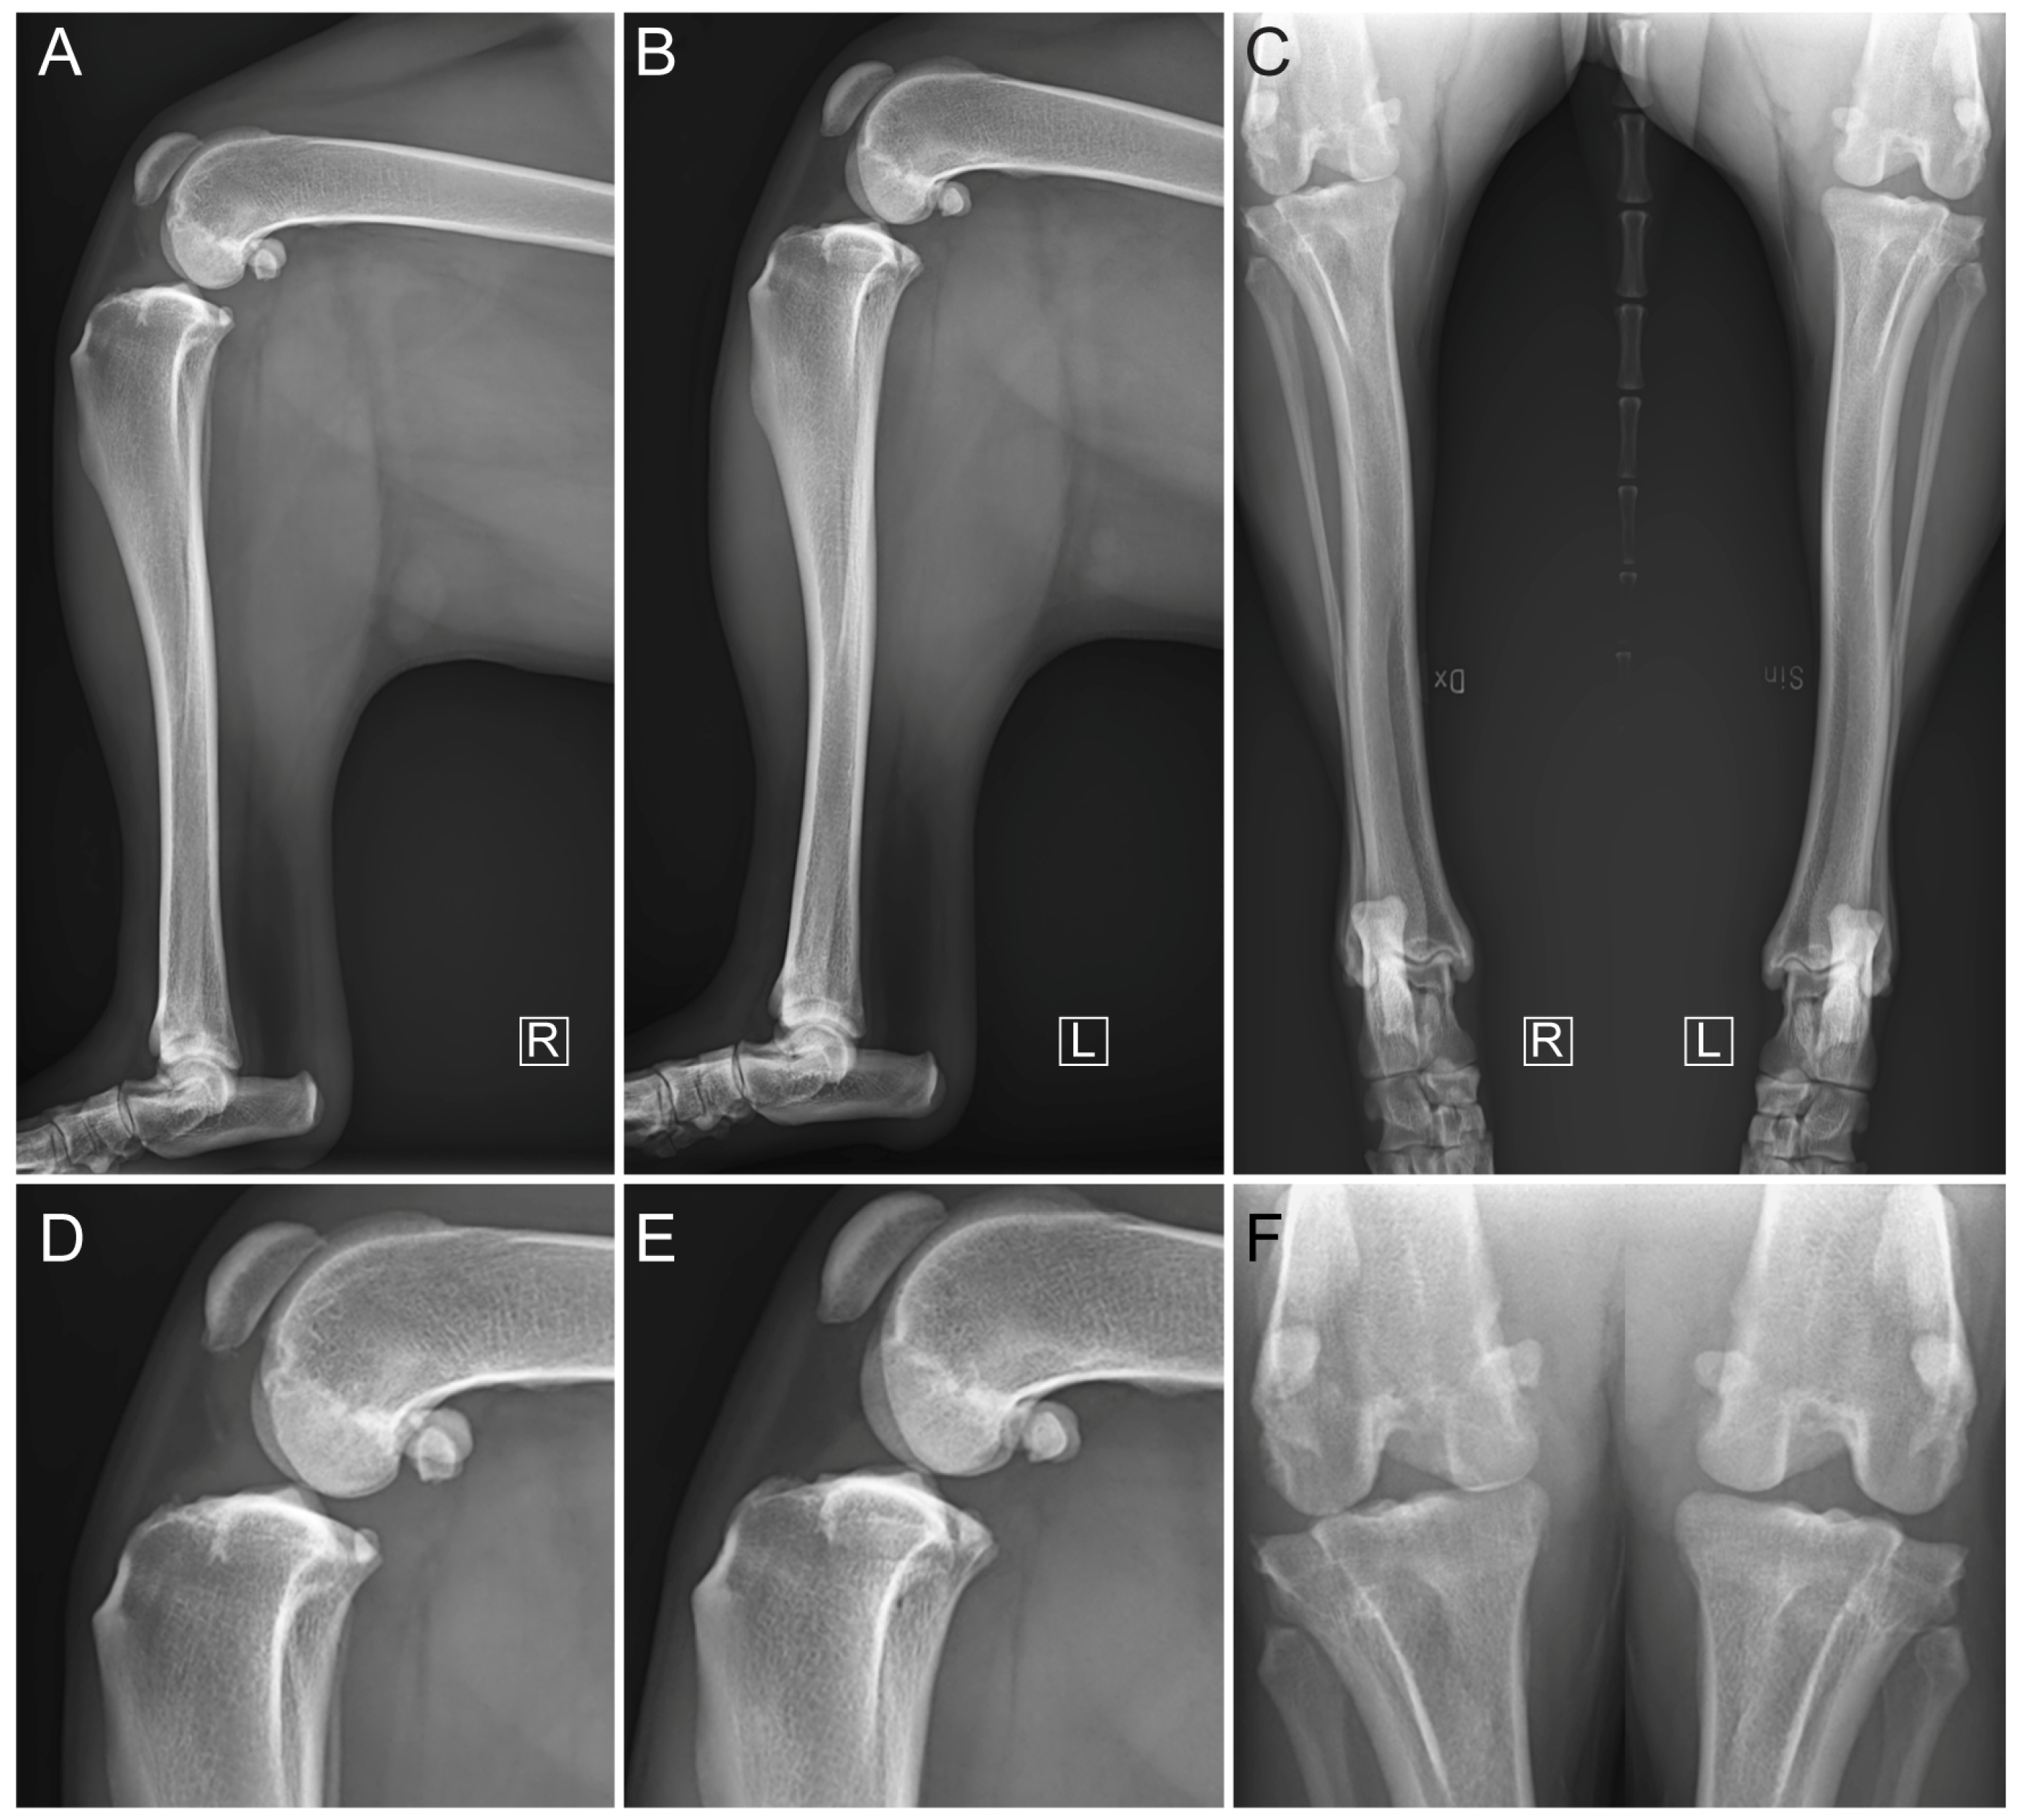

2.4. Surgical Treatment